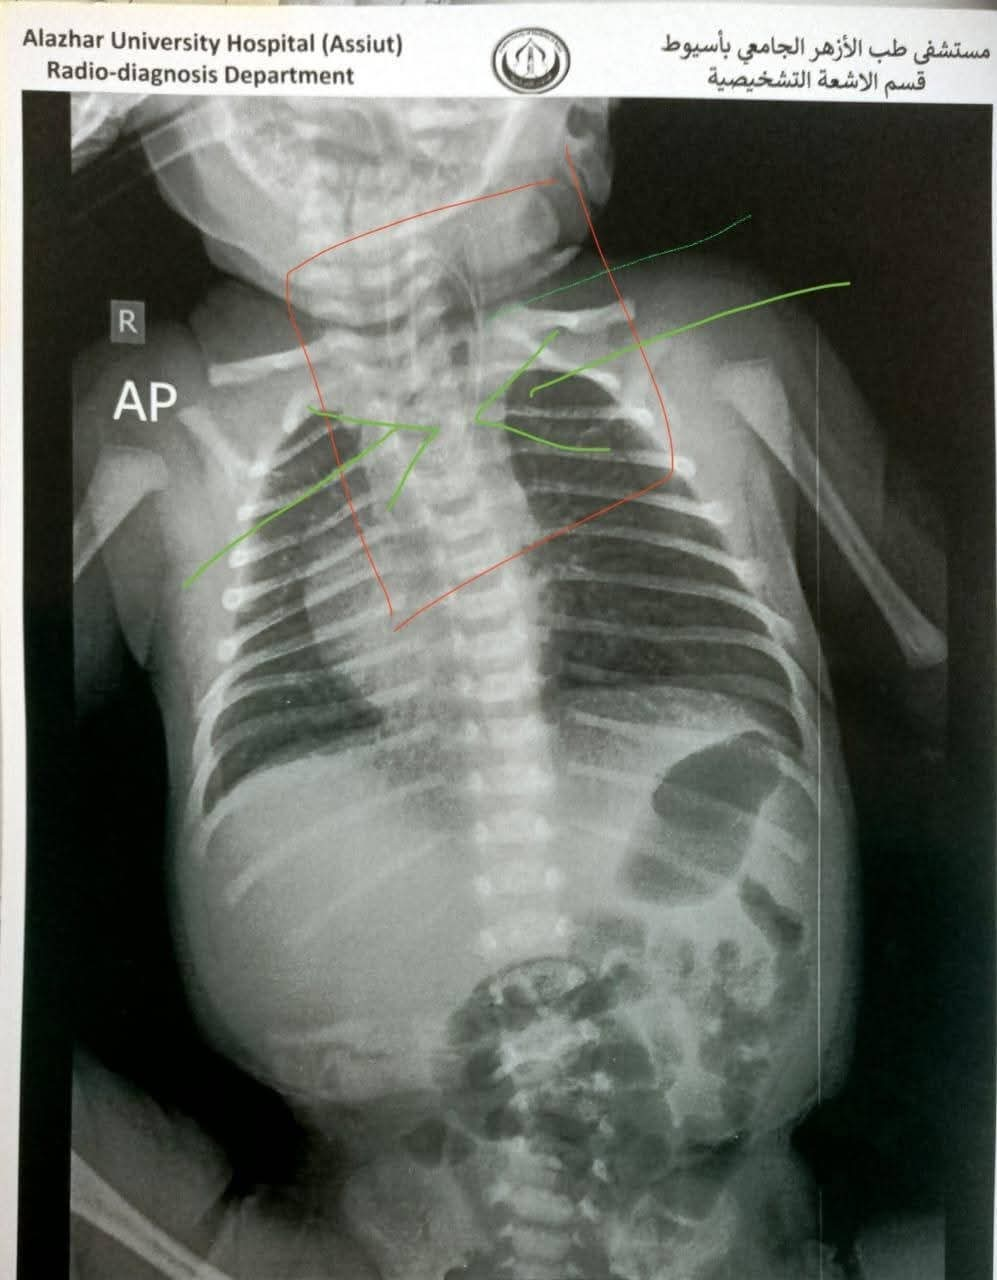

وأوضح عميد كلية الطب ورئيس مجلس إدارة مستشفى الأزهر الجامعي بأسيوط أن نتائج الفحوصات أكدت وجود انسداد كامل بالمريء وناسور بحجم كبير بين المريء والقصبة الهوائية، مما استدعى التدخل الفوري لإنقاذ حياة الطفل. وتم تجهيز غرفة العمليات لإجراء الجراحة التي تُعد من أعقد جراحات الأطفال، وتتطلب دقة ومهارة عالية.

وأكد عميد كلية الطب أن الفريق الطبي تمكّن، خلال 4 ساعات من العمل فصل الناسور تمامًا عن القصبة الهوائية، وإعادة توصيل المريء بنجاح، إلى جانب تركيب قسطرة وريدية مركزية لضمان استمرار تقديم العلاج اللازم للرضيع عقب الجراحة. وخرج الطفل من غرفة العمليات في حالة مستقرة.